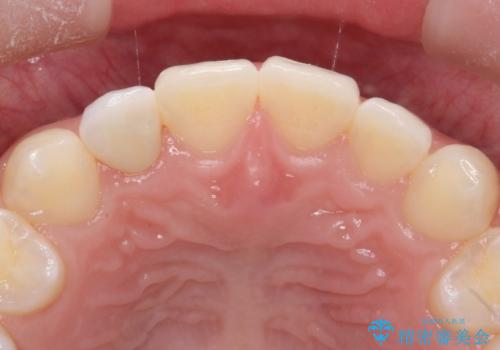

- 上の歯の隙間が気になるとのことで来院されました。

上顎の正中に隙間があり、右上の2番目の歯が通常の歯より小さい矮小歯でした。

正中の隙間をインビザライン矯正で閉鎖して、右上の2番目の歯にはセラミックを装着する計画としました。